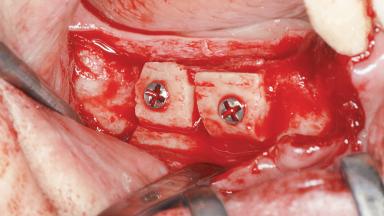

Bilateral Horizontal Ridge Augmentation with Block Bone Grafts Using a Piezoelectric Device for Fixed Implant Restoration

A woman in her mid-fifties was referred by a dental student for dental implant placement. Both posterior segments of the mandible had been edentulous for more than 4 years, the only residual tooth being the right lower first premolar. The patient had used a removable partial denture but was not entirely satisfied with its function. The clinical examination revealed a sharp edentulous ridge in both posterior segments of the mandible, and the patient was told that it would not be possible to insert implants into this thin edentulous ridge without significant augmentation of the alveolar ridge. Her medical history revealed no significant findings and no underlying disease that might have complicated surgical procedures. During the presurgical examination, the patient reported that she was a little apprehensive about bone grafting. After being informed about the surgical procedures and potential postoperative complications, she accepted the proposed surgical plan of bone grafting and subsequent placement of implants.